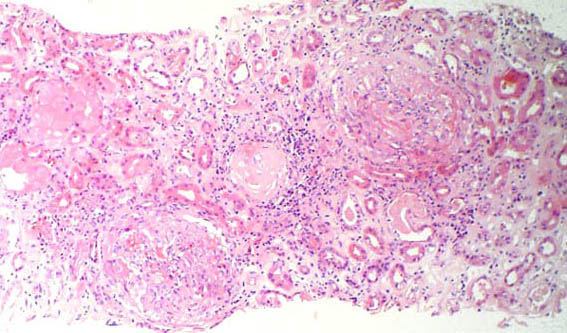

The patient is a 18-year-old woman. History of ESKD due to Alport syndrome. She was living related donor kidney transplanted. Immunosuppression: tacrolimus, prednisone, mycophenolate. Nine months after transplantation there is edema of lower limbs, fever, oliguria, asthenia and adynamia. On examination: BP 150/90, HR: 100. Facial and lower limb edema. There are no other abnormalities on physical examination.

Laboratory tests: serum creatinine 3.5 mg/dL; BUN 52 mg/dL; PCR 8.1, ESR 48. Leukocytes 10,500, neutrophils: 93%, lymphocytes: 3%, platelets 194,000. Hb 10.4 Hto 31. Uroanalysis: density: 1.010, pH 6, proteins 500 mg/dL, nitrites: negative, erythrocytes 21-30/hpf, leukocytes 10-20/hpf. Uroculture: negative. Renal Doppler echo: increased cortical echogenicity, resistance index: 0.65, no thrombosis or stenosis. ANAS, anti-DNA and ANCAs: Negative. C3 and C4 serum levels: normal.

An allograft kidney biopsy was done. See the images.

Figure 1. H&E, X100.